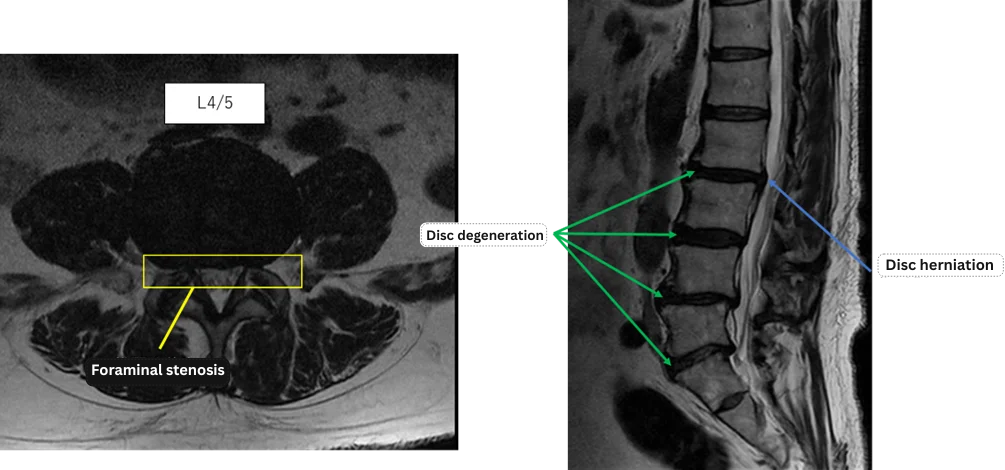

Imaging and findings

L1/2: No abnormalities

L2/3: Disc herniation, disc degeneration

L3/4: Disc degeneration

L4/5: Disc degeneration, bilateral foraminal stenosis

L5/S: Disc degeneration, bilateral foraminal stenosis

The above findings were also observed on the imaging.

Disc herniation, disc degeneration, and bilateral foraminal stenosis at L2/3, L3/4, L4/5, and L5/S are considered highly likely to be the cause of the primary symptoms.